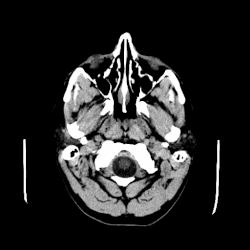

A colloid cyst is a non-malignant tumor in the brain. It consists of a gelatinous material contained within a membrane of epithelial tissue. It is almost always found just posterior to the foramen of Monro in the anterior aspect of the third ventricle, originating from the roof of the ventricle. Because of its location, it can cause obstructive hydrocephalus and increased intracranial pressure. Colloid cysts represent 0.5–1.0% of intracranial tumors.[1]

Colloid cysts can be diagnosed by symptoms presented. Additional testing is required and the colloid cyst symptoms can resemble those of other diseases. MRI and CT scans are often used to confirm diagnosis.[5]